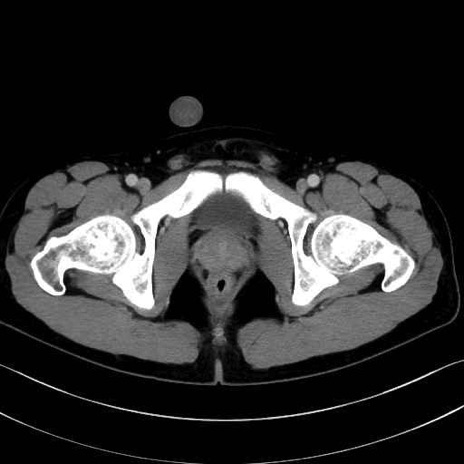

中間広筋 (Vastus intermedius)

6. 大腿内側(内転筋群)

恥骨筋 (Pectineus)